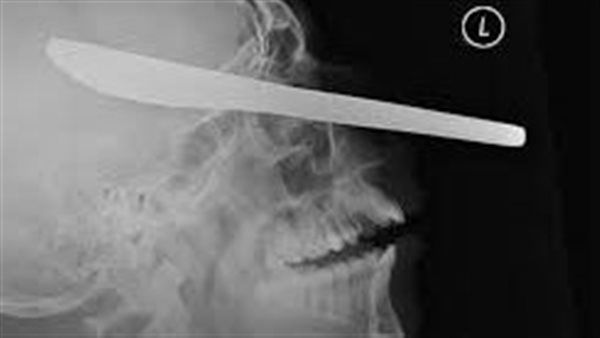

وأظهرت الأشعة السينية والأشعة المقطعية لجمجمته أن المسمار اخترق الفص الأمامي للدماغ، وهي منطقة حيوية للحركة واللغة. وتسبب بعد ذلك في حدوث نزيف امتد إلى مناطق الدماغ المجاورة.